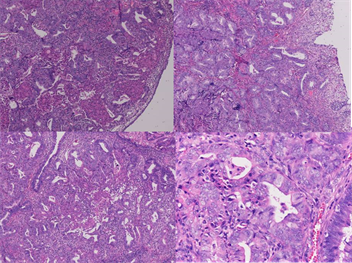

On low-power microscopic examination (Figure 1): The lesions were composed of a proliferation of atypical endometrial glands separated by varying amounts of cellular smooth-muscle Stroma. The boundary between the APA and adjacent stroma was usually sharp. Some irregular glands were lined with branched and back-to-back arrangements, and ranged from small simple glands to more irregularly shaped glands and large cysts. Cuff-like appearance was not found around irregular glands.

One high-power microscopic examination (Figure 1): Part of gland cells showed minimal to moderate nuclear atypical. Morularsquamous metaplasia was not present in all two cases. Small foci of intraluminal necrosis didn’t occur in all two cases. Epithelial mitotic figures were rare in one case, but no atypical mitotic figure was identified. The stromal component consisted of smooth

Figure 1. HE staining in APA.

muscle which was characterized by the typical small fusiform cells with eosinophilic cytoplasm and benign nuclear features . But the mitotic figures of cellular smooth-muscle were rare and did not exceed 2 per 10 hpt when averaged over 40 hpt. Immunohistochemical staining (Figure 2): The stromal cells in all of the 2 APA Cases in which immunohistochemical staining was performed showed staining for SMA, Desmin but without CD10 and h-Caldesmon. The lesion glands showed prominent staining of the glandular epithelium with estrogen receptor(ER) and progesterone receptor(PR), but not showed P53 and CEA, the positive index of Ki67 < 5%.